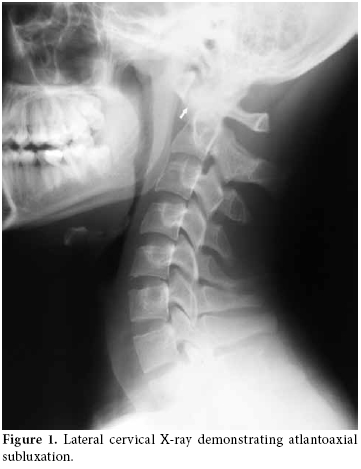

The lateral view of the cervical radiography revealed atlantoaxial subluxation (figure 1). On the computed tomography (CT), the distance between the axis and dens clearly widened as it measured approximately 10 mm (figure 2). The T1-weighted magnetic resonance imaging (MRI) showed a widened atlantodental space (figure 3a). At this localization, T2-weighted images revealed a heterogeneous hyperintense lesion, and at C2, C3, and C4 levels increased retropharyngeal soft tissue thickness appeared (figure 3b). In postcontrast T1-weighted sequences, the increased retropharyngeal soft tissue thickness and lesion showed heterogenous enhancement which was interpreted as soft tissue infection and abscess, respectively (figure 3c).

Radiological investigation plays an important role in the diagnosis. Plain anteroposterior and lateral radiographs may show asymmetry of the facet joints and increased predental space.[8] Both CT scanning and MRI are diagnostically used.[10] In our case, retropharyngeal soft tissue swelling was demonstrated. Dynamic studies may be necessary, but they may cause neurological complications.[14]